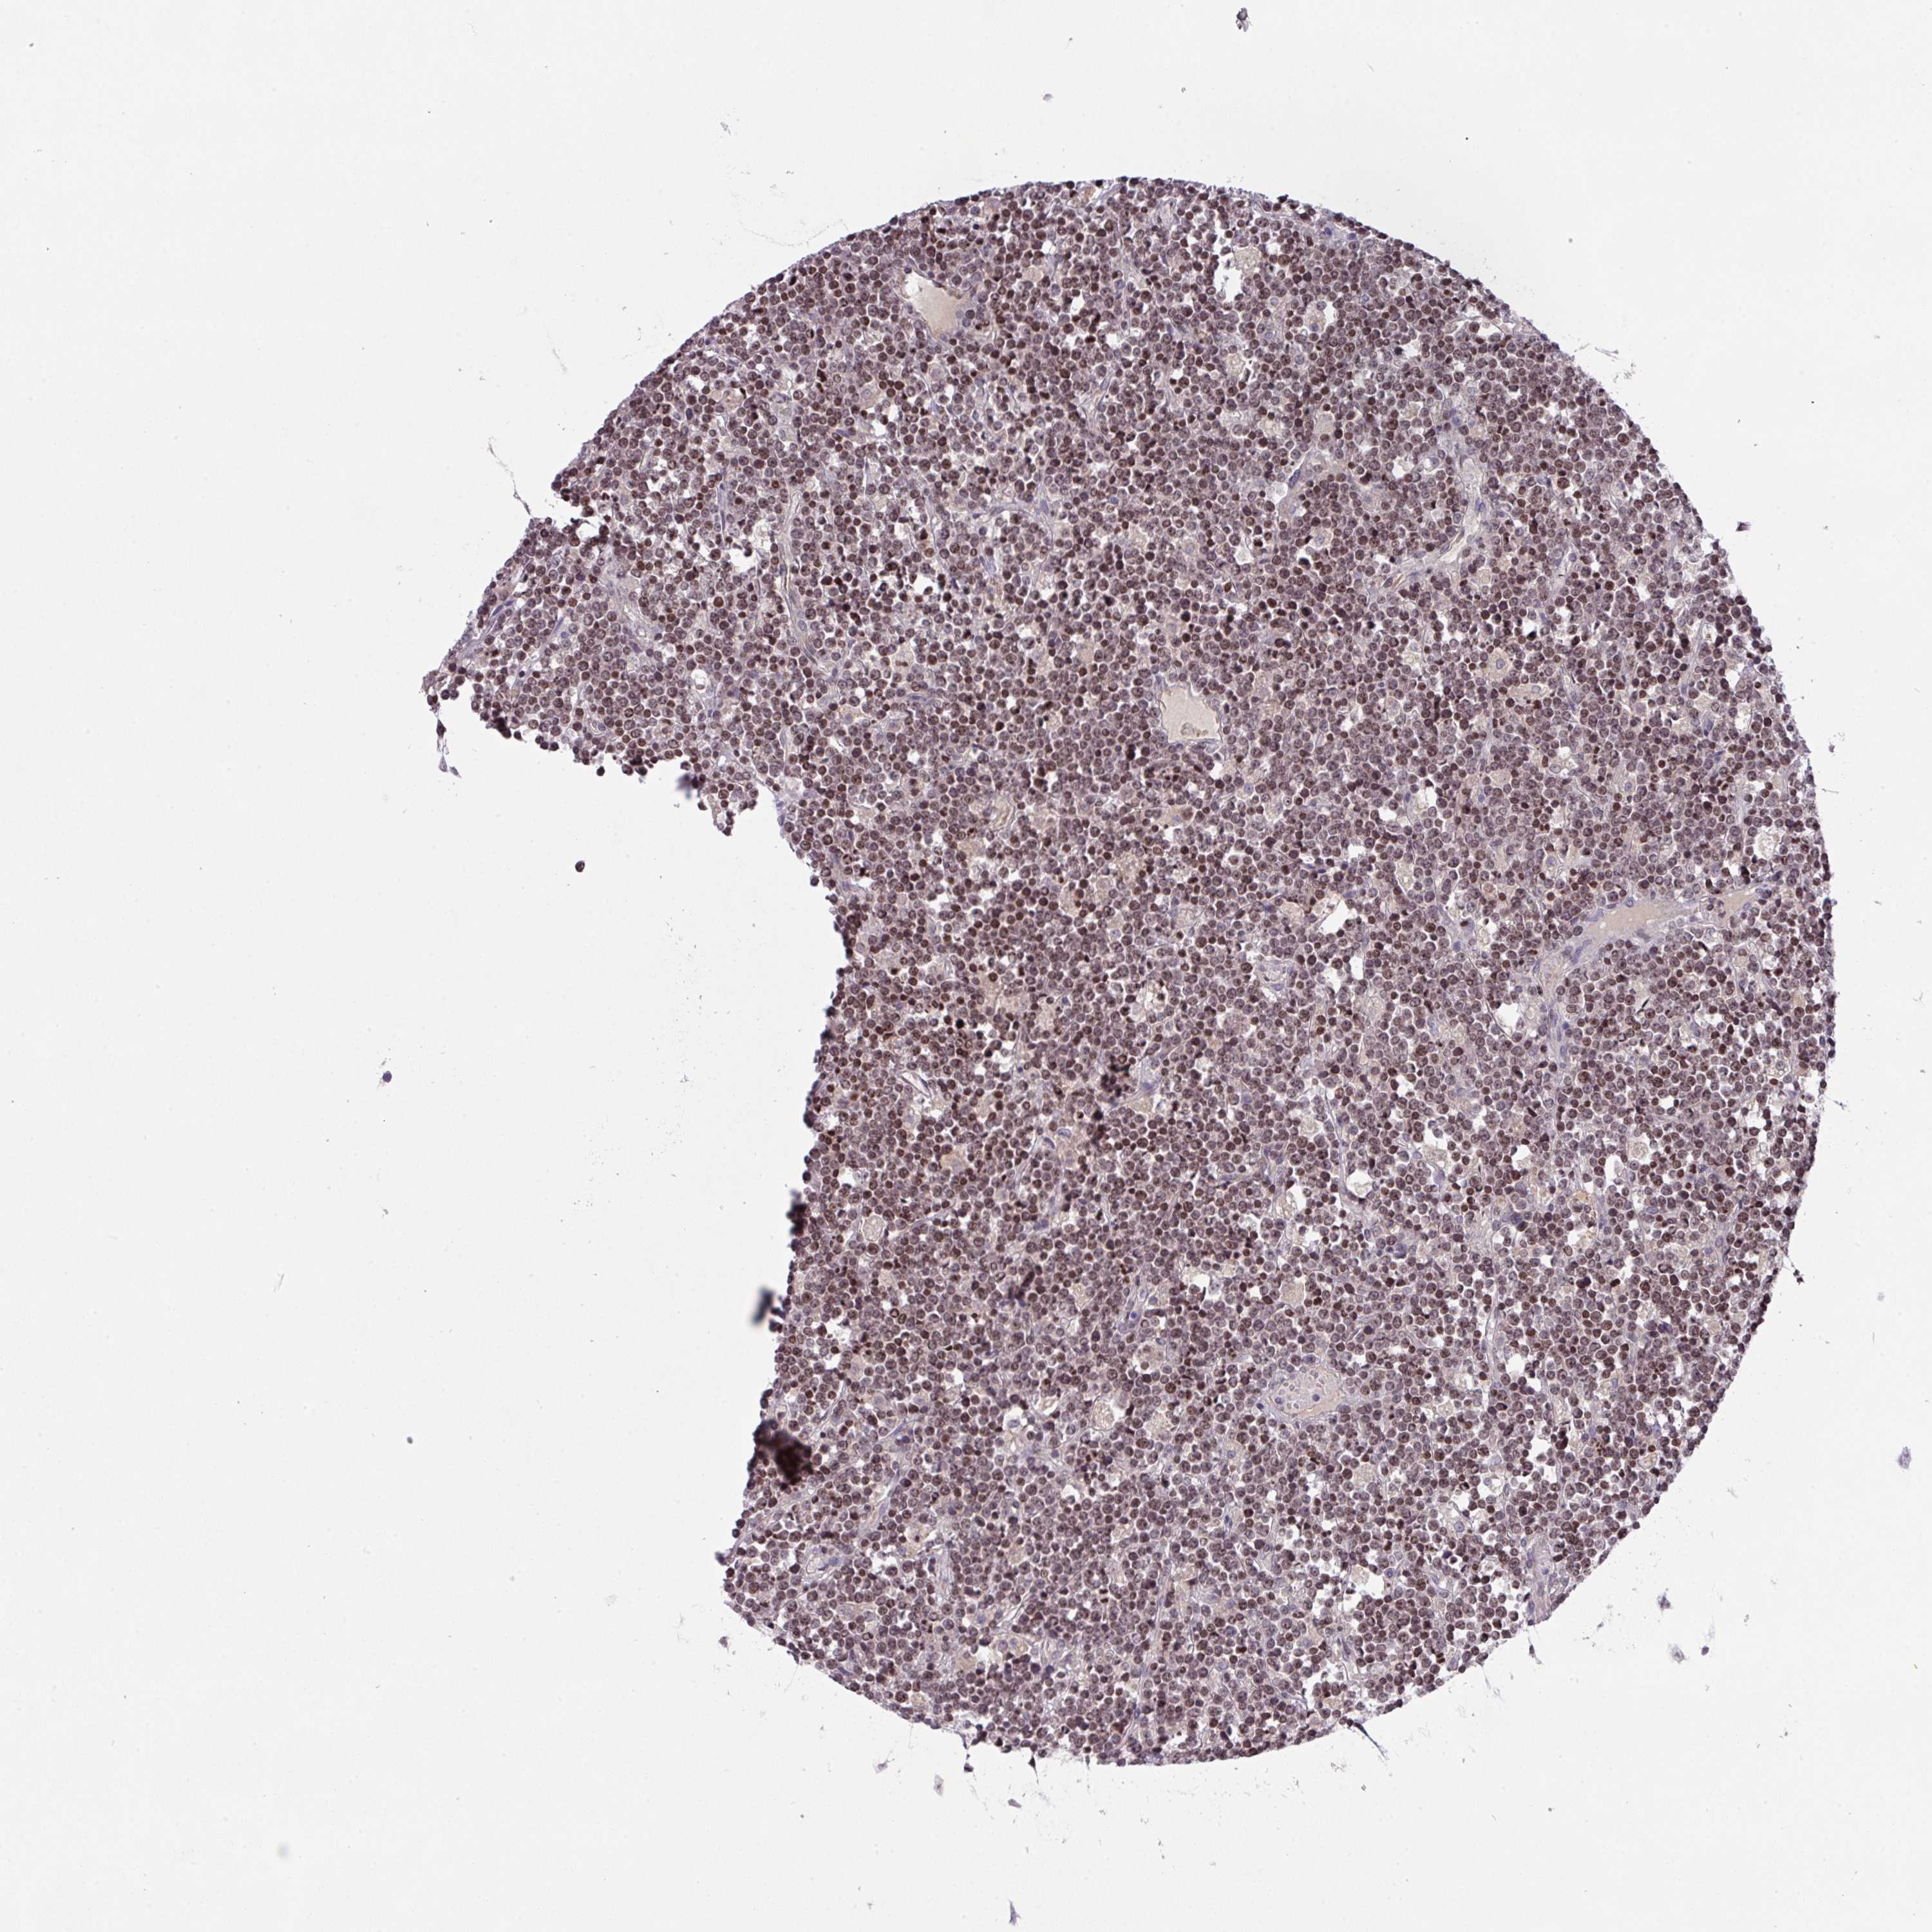

LYMPHOMA - Protein expressioni

A mouse-over function shows sample information and annotation data. Click on an image to view it in a full screen mode. Samples can be filtered based on level of antibody staining by selecting one or several of the following categories: high, medium, low and not detected. The assay and annotation is described here.

Antibody stainingi

Antibody staining in the annotated cell types in the current human tissue is reported as not detected, low, medium, or high, based on conventional immunohistochemistry profiling in selected tissues. This score is based on the combination of the staining intensity and fraction of stained cells.

Each image is clickable and will lead to virtual microscopy that enables deeper exploration of all samples and also displays staining intensity scores, fraction scores and subcellular localization as well as patient and tissue information for each sample.

Antibody HPA051421

Antibody HPA054639

Malignant lymphoma, non-Hodgkin's type, Low grade

Malignant lymphoma, non-Hodgkin's type, High grade

Hodgkin's disease, NOS